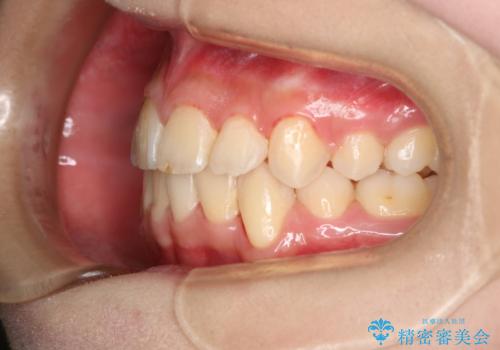

出っ歯と深い噛み合わせ:抜歯矯正で口元スッキリ!

- 出っ歯が気になるとご相談にいらした方です。抜歯して歯を並べました。深かった噛み合わせも改善させることが出来ました。

噛み合わせが元々深い方は一般的に噛む力が強く、治療に時間がかかる傾向にあります。治療前の想定よりも短期間でスムーズに治療を終える事ができ、大変喜んでいただけました。リテーナーによる保定もしっかり行っていただいており、後戻りなく快適にすごして頂けているとのことです。